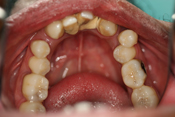

WORST TEETH Pictures from Warren Dentistry

This can happen to your teeth when proper Dental Hygiene is not practiced.

Patient 1